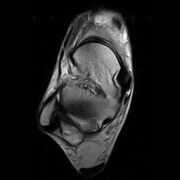

The Esaote S-scan Open MRI system is widely used in clinical and research settings for musculoskeletal imaging, offering ergonomic design, real-time imaging, and an open, patient-friendly experience. ImagPros provides expert support to ensure a smooth purchasing process and is committed to your imaging success.